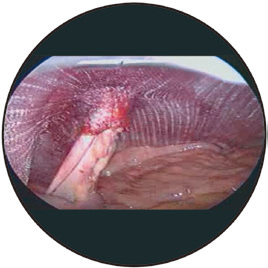

■獨(dú)一無(wú)二的3D袖口設(shè)計(jì),依靠編織技術(shù),無(wú)縫連接,是化平面為立體的卓越產(chǎn)品,保證術(shù)后復(fù)發(fā)率最低。